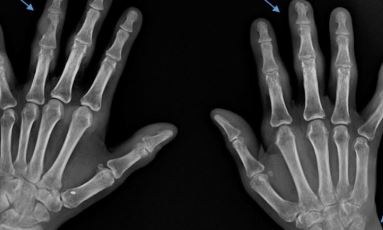

손가락 류마티스 관절염 진단방법

손가락 류마티스 관절염 진단은 x-ray검사, 관절초음파 검사,MRI검사 등이 진행될수 있으며 2020년9월 부터는 류마티스 관절염 진단하기 위해 검사중 "항CCP항체검사"가 건강보험 적용으로 기존보다 낮은 비용으로 검사가 가능해진다.